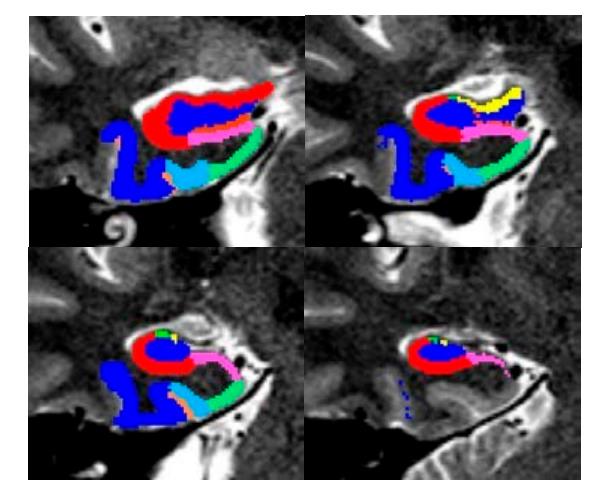

Resting-state functional connectivity is calculated as Z-transformed correlation coefficient between pre-processed time series, using the CONN toolbox [143] and connectivity between seed region time series and each grey matter voxel is calculated to create connectivity maps for each seed region. In addition to the commonly used seed-based analysis, we utilize generalized psychophysiological interaction (gPPI) for task-based analyses, which allows us to understand how brain regions interact in a task-dependent manner with greater sensitivity and specificity than the standard PPI (sPPI) [144,145]. For both types of functional connectivity, we utilize seed-region approaches, defined using probabilistic atlases derived from structural tracings, with the following seeds: laterobasal, centromedial and superficial sub-regions of the AMG (Figure 5) [146–149], anterior and posterior regions of the HIPP (Figure 6) [150], and inferior and superior parts of the VS [151,152]. The resulting T maps are then thresholded at p < 0.05, using random field theory to correct for the multiple voxel comparisons based on spatial smoothness [153,154] to identify brain regions where the groups have differences in connectivity.